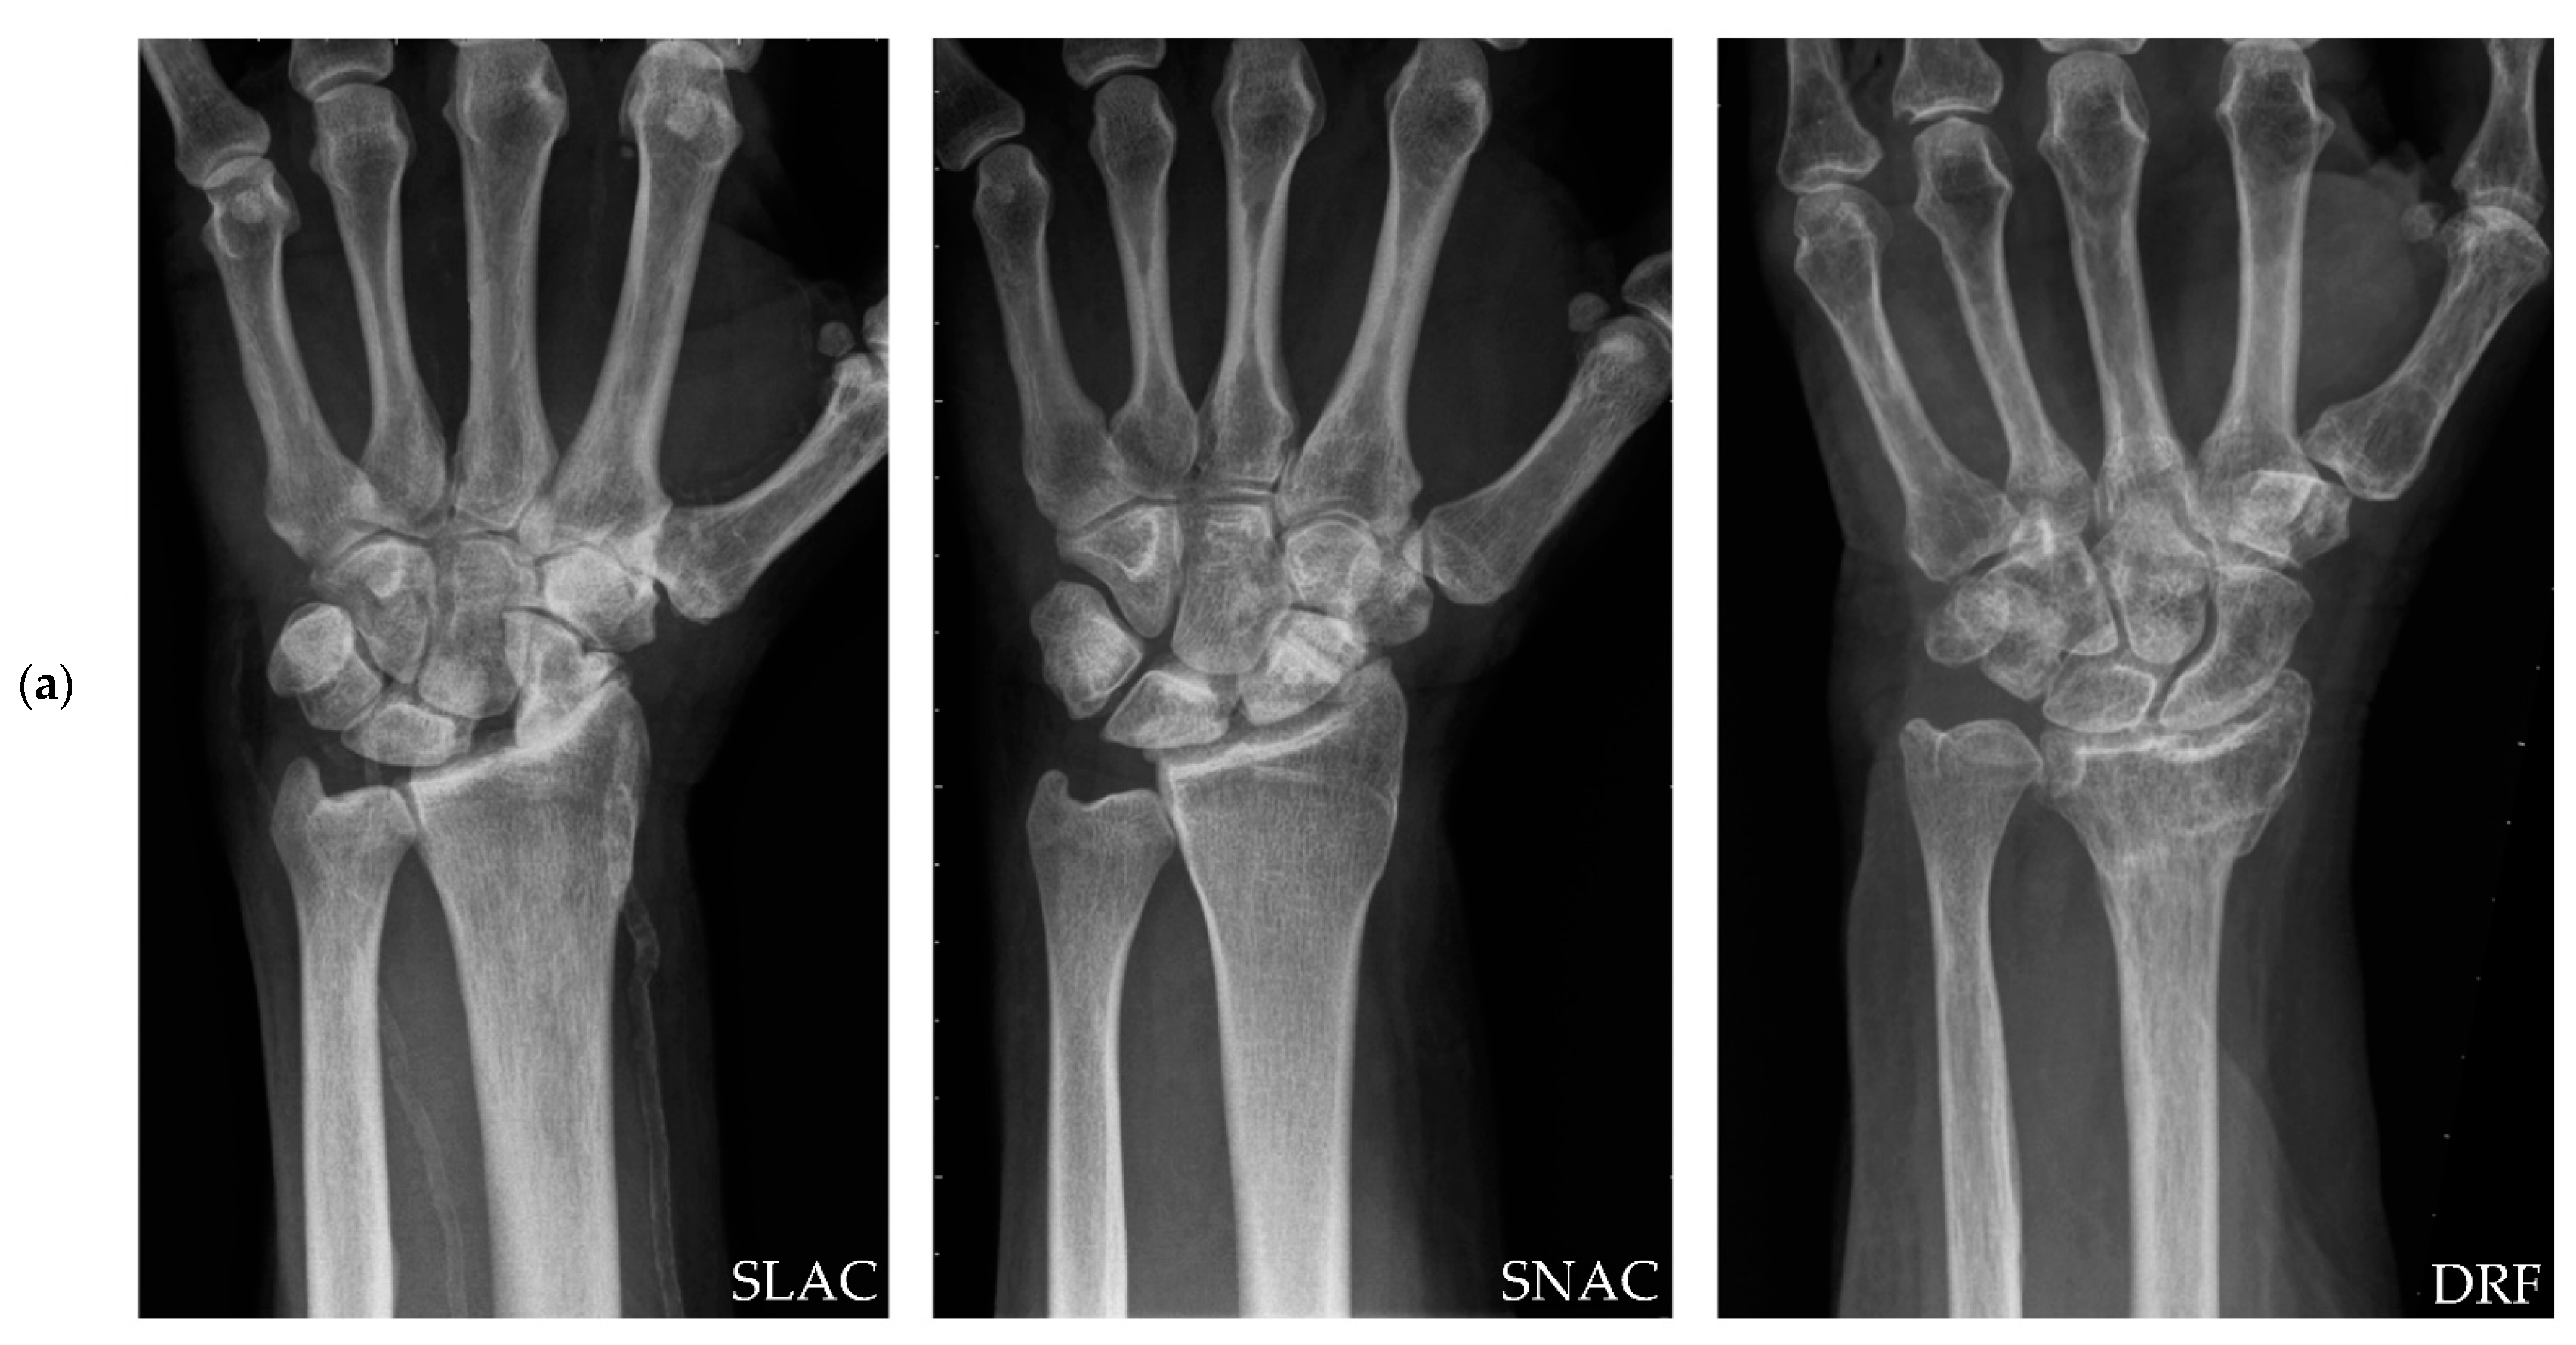

Total Wrist Arthroplasty for Posttraumatic Wrist Osteoarthritis: A Cohort Study Comparing Three Indications

| Parameters | SLAC | SNAC | DRF | p-Value |

| Patients | 13 | 11 | 8 | - |

| Wrists | 13 | 11 | 8 | - |

| Age | 63.4 ± 8.0 | 56.7 ± 9.9 | 57.5 ± 8.8 | 0.16 1 |